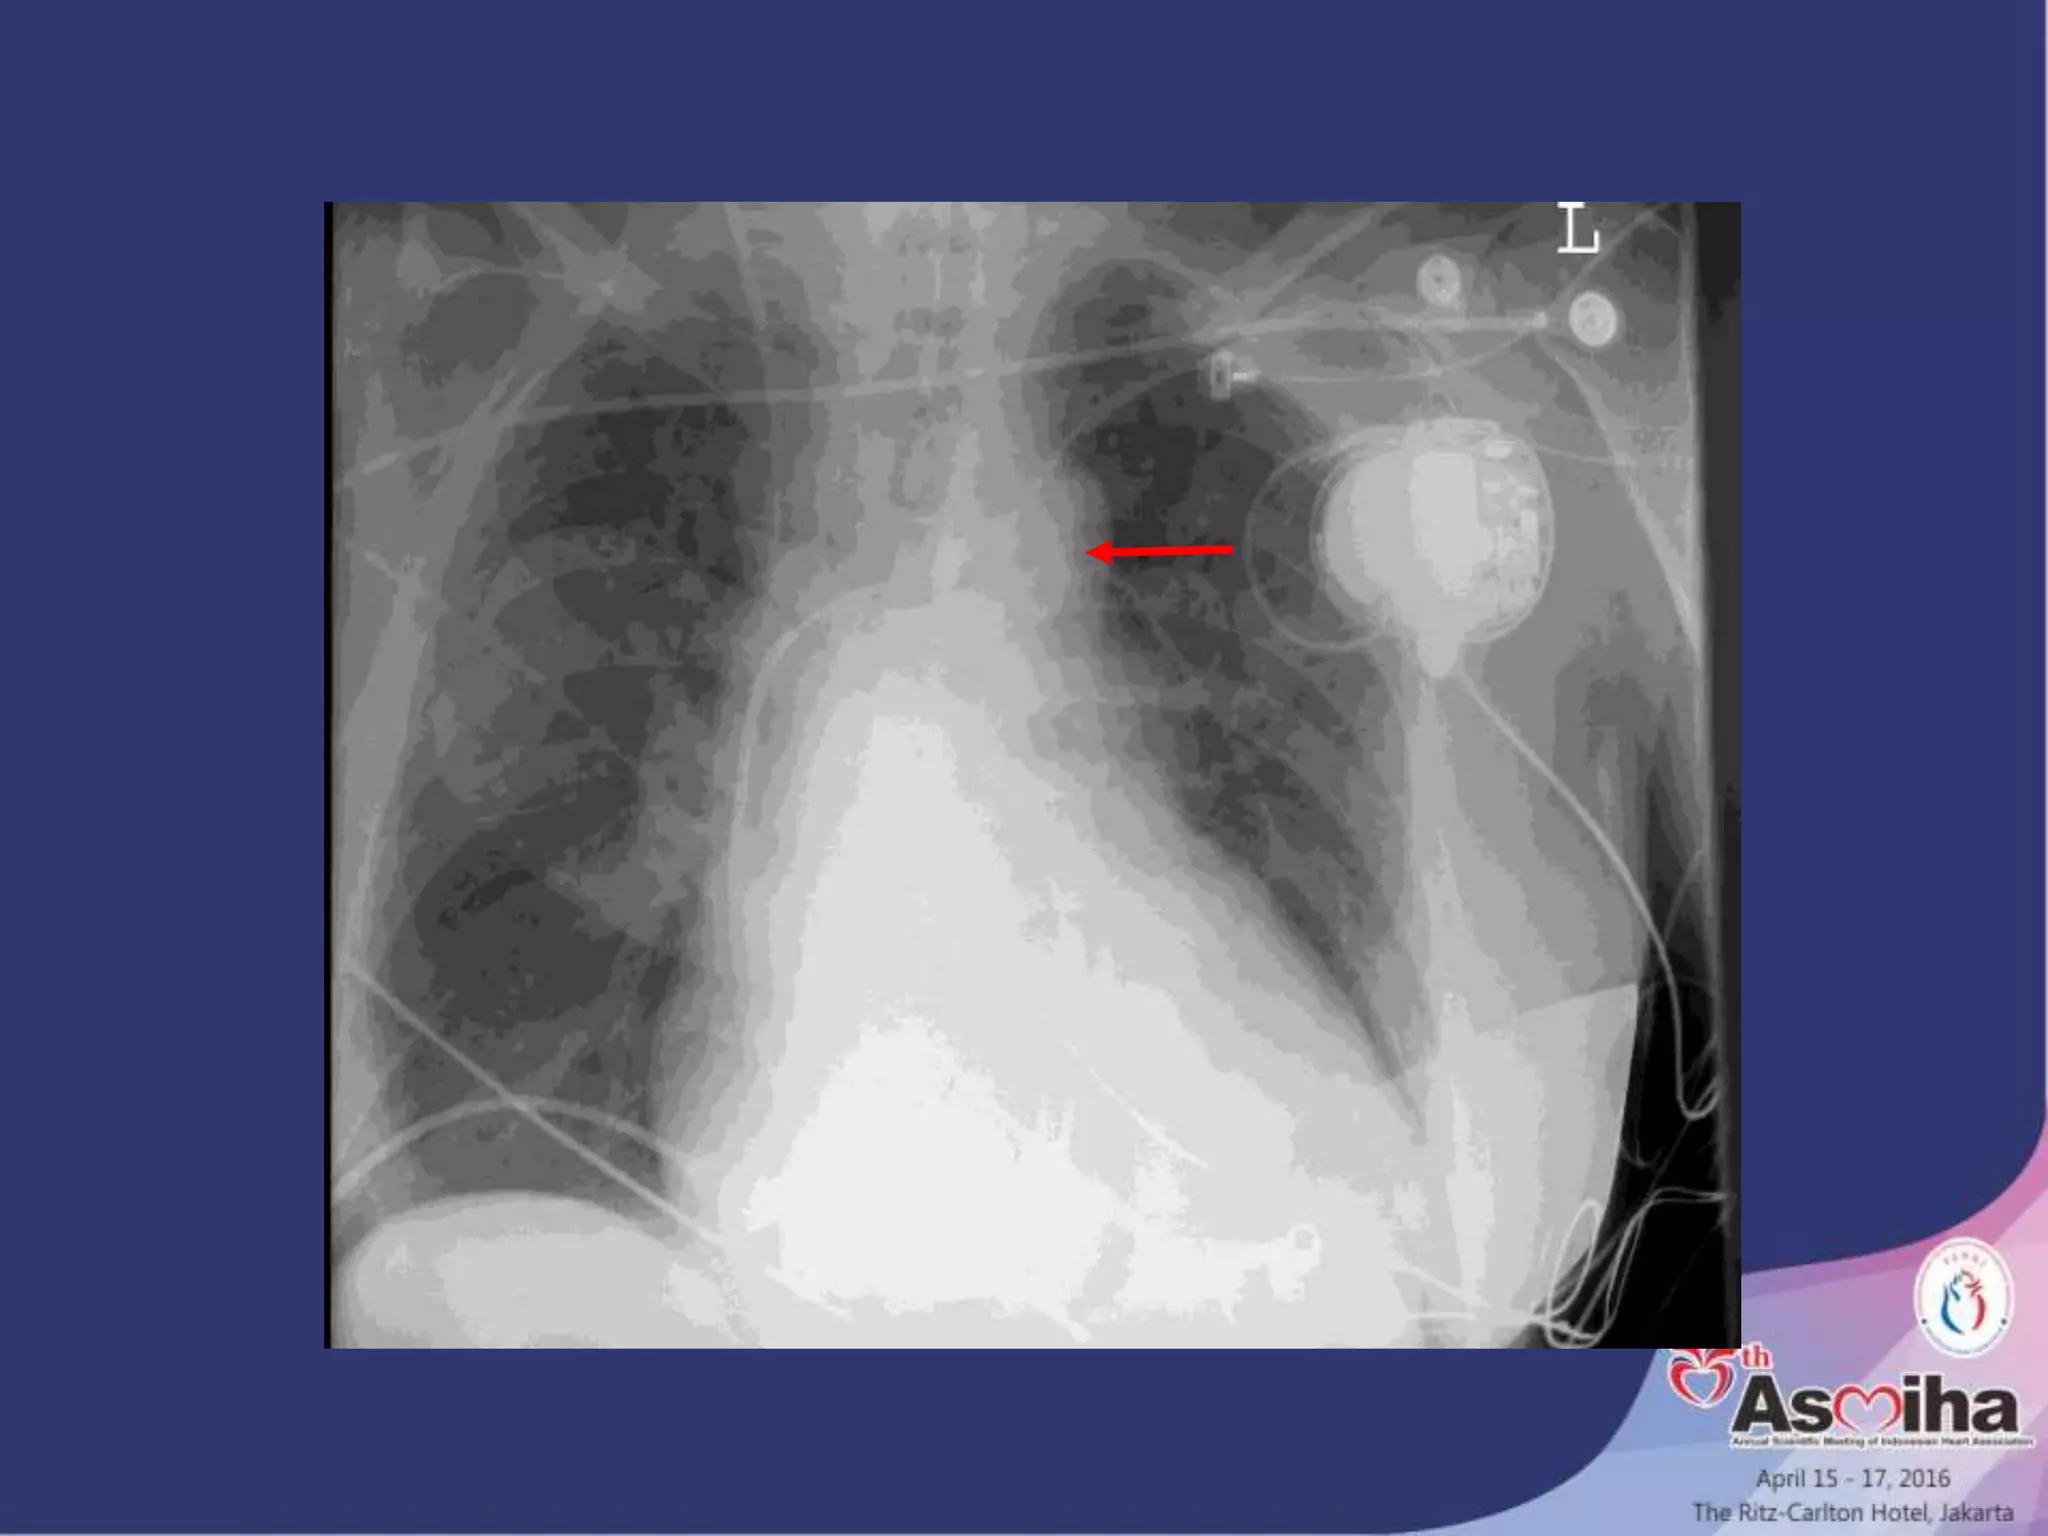

Placement

• Placed percutaneously or surgically with or without a sheath

via the femoral artery.

• Advanced into aorta under flouroscopy until the tip is about

1cm distal to the origin of the left subclavian a.

• Cathater locations more proximal than this compromise flow

to the vessels of the aortic arch.

• More distal locations attenuate the hemodynamic benefits of

the IABP and can potentially compromise renal blood flow.